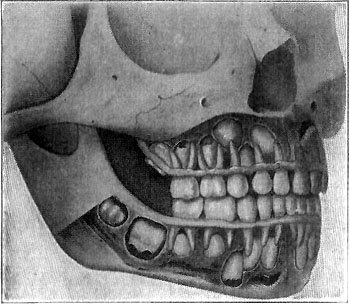

282 The Replacing of the Milk Teeth

284 A Tooth-Brush Drill